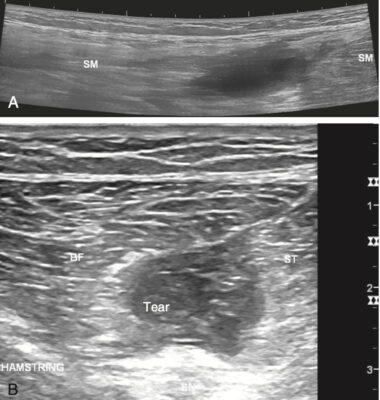

- Siêu âm và chụp cộng hưởng từ được sử dụng để xác định mức độ tổn thương và xác định tổn thương đứt hoàn toàn ở phần gần, đặc biệt là siêu âm do kinh tế hơn.